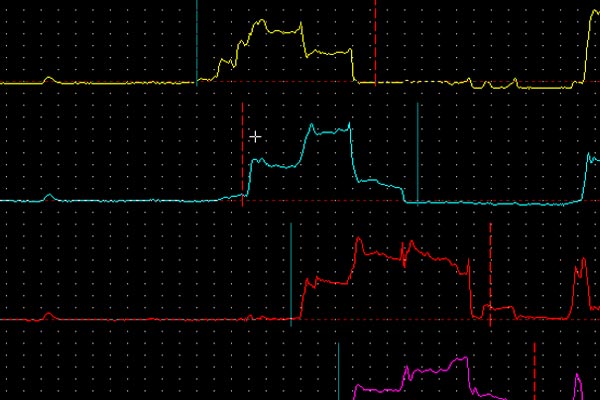

Biofeedback Anorretal

É um método de treinamento esfincteriano supervisionado utilizado no tratamento de distúrbios ao nível do aparelho esfincteriano do ânus e períneo [...].

Eletroneuroestimulação Anorretal

O tratamento pela EE é realizado com equipamento destinado às modalidades eletroterápicas. Utiliza uma tecnologia de microcomputadores [...].